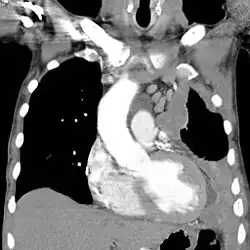

Left-sided mesothelioma (seen on the right of the image): chest CT

The most common diseases associated with chronic asbestos exposure are asbestosis (scarring of the lungs due to asbestos inhalation) and mesothelioma (cancer associated with asbestos).[10] Mesothelioma is an aggressive form of cancer and often leads to a life expectancy of less than 12 months after diagnosis.[118]